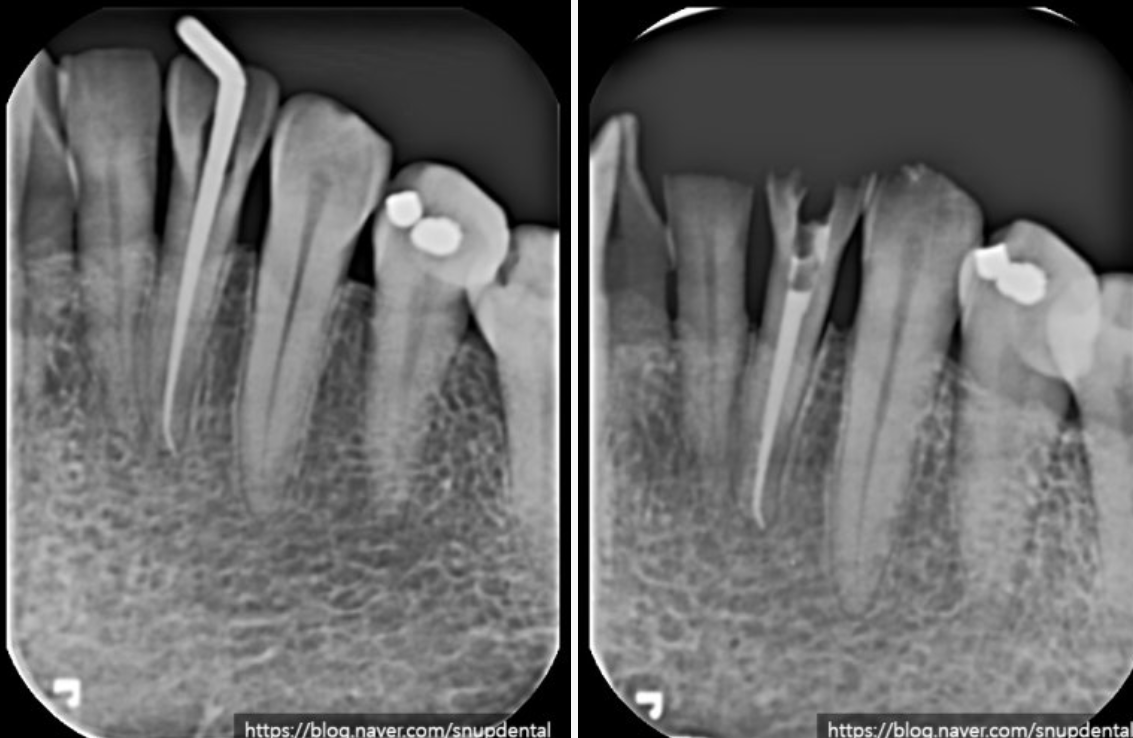

오른쪽 아래 두 번째 어금니 불편감(통증) 호소

아말감 부분 파절 및 이차우식 소견

치아 crack 소견(굵은 화살표)

왼쪽 아래 두 번째 앞니(#32)

충혈(hyperemia) 증상

단순히 색만 변한 경우에는 지켜보는 경우도 있으나 위 환자의 경우 치수염 증상이 나타났고 비가역적 치수염으로 자연적으로 회복이 불가능하다고 판단되어 근관치료(신경치료)를 진행하였습니다.

주변 치질이 건전하기에 우선 근관치료 후 레진으로 마무리할 예정입니다.